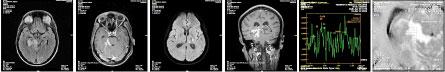

The baseline CT as well as MRI was normal for only two (1.9%) patients. Eleven (10.9%) patients had completed both baseline CT and MRI investigation. MRI was more sensitive in picking up a larger number of Tuberculoma lesions, infarcts, vasogenic edema and meningeal enhancement as compared to CT (Fig 1).

1-a1-b1-c1-d1-e1-f

Fig 1 — MRI - a, b, c, d, e, f: Axial FLAIR, Axial T1 Contrast enhanced, Axial DWI, Coronal T1 Contrast enhanced Wt and MR Spectroscopy images. Multiple ring enhancing altered signal intensity lesions in bilateral cerebral and cerebellar hemispheres with mild perilesional edema, displaying hypo intense signal intensity on T1 and hyper intense signal intensity on FLAIR sequences. Enhancing lesion with conglomeration in the ambient and quadrigeminal cisterns with thick enhancing exudates. Diffuse restriction focus in left thalamus - TUBERCULOMAS WITH TUBERCULOUS MENINGITIS AND VASCULITIS.